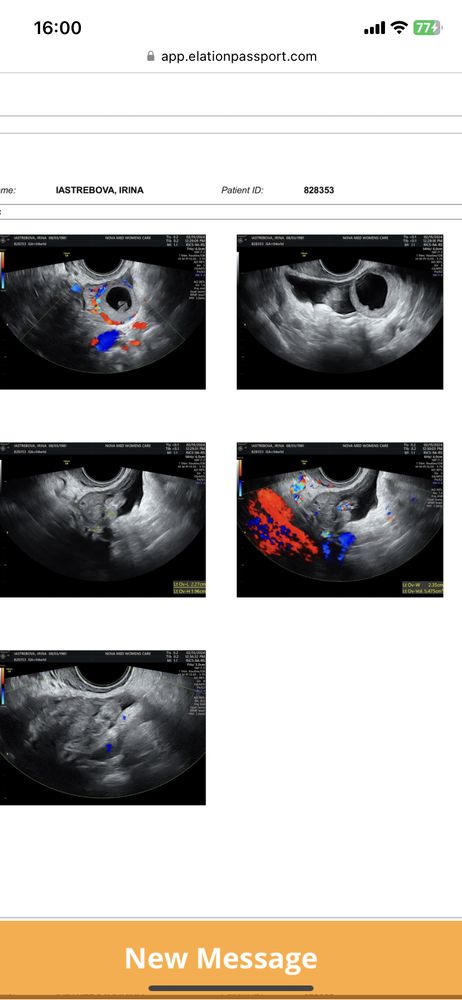

Есть же плодное яйцо: gs rempen это оно. Соответствует сроку. Всё ок.

Ну тут написано, что 0,66 см плодное яйцо, что соответствует 5 неделям и 3 дням

Ирина Богданова, и как я поняла ЖТ на правом яичнике

15.02.2024

Ольга, да желтое тело на правом я ,вы абсолютно правы ,спасибо я даже не прочитала запаниковала

Написано "предположительно плодное яйцо или свободная жидкость". Я бы переделала, может, узист такой.